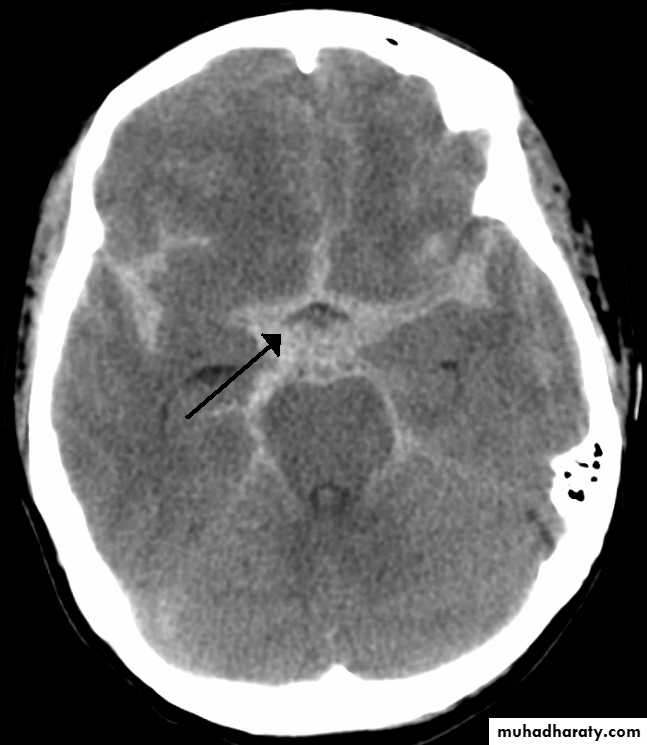

A- investigation:CT /MRI the best to detect heamoorage is brain CT

computed tomography (CT) scan:will detect subarachnoid blood in more than 90% of patientsCSF examination may be needed if CT is negative which will reveled grossly bloody or the supernatant of the centrifuged CSF becomes yellow-tinged (xanthochromic) within several hours (certainly by 12 hours) following the hemorrhage